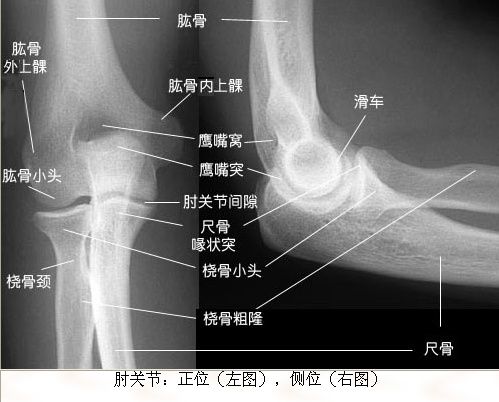

• 肘关节脱位伴骨折 attach_img

• jiangtaog123 2010-7-12

• 患者女35岁 ,高处坠落,左臂肘关节脱位伴桡骨头骨折,淤血凝结,青紫蛮重,痛疼剧烈。予以复位,以下是复位前后的片子 整复后外敷屈曲位固定,1骨肽针1合+NS250 GS250+脉络宁2支 ...  阅读全文>